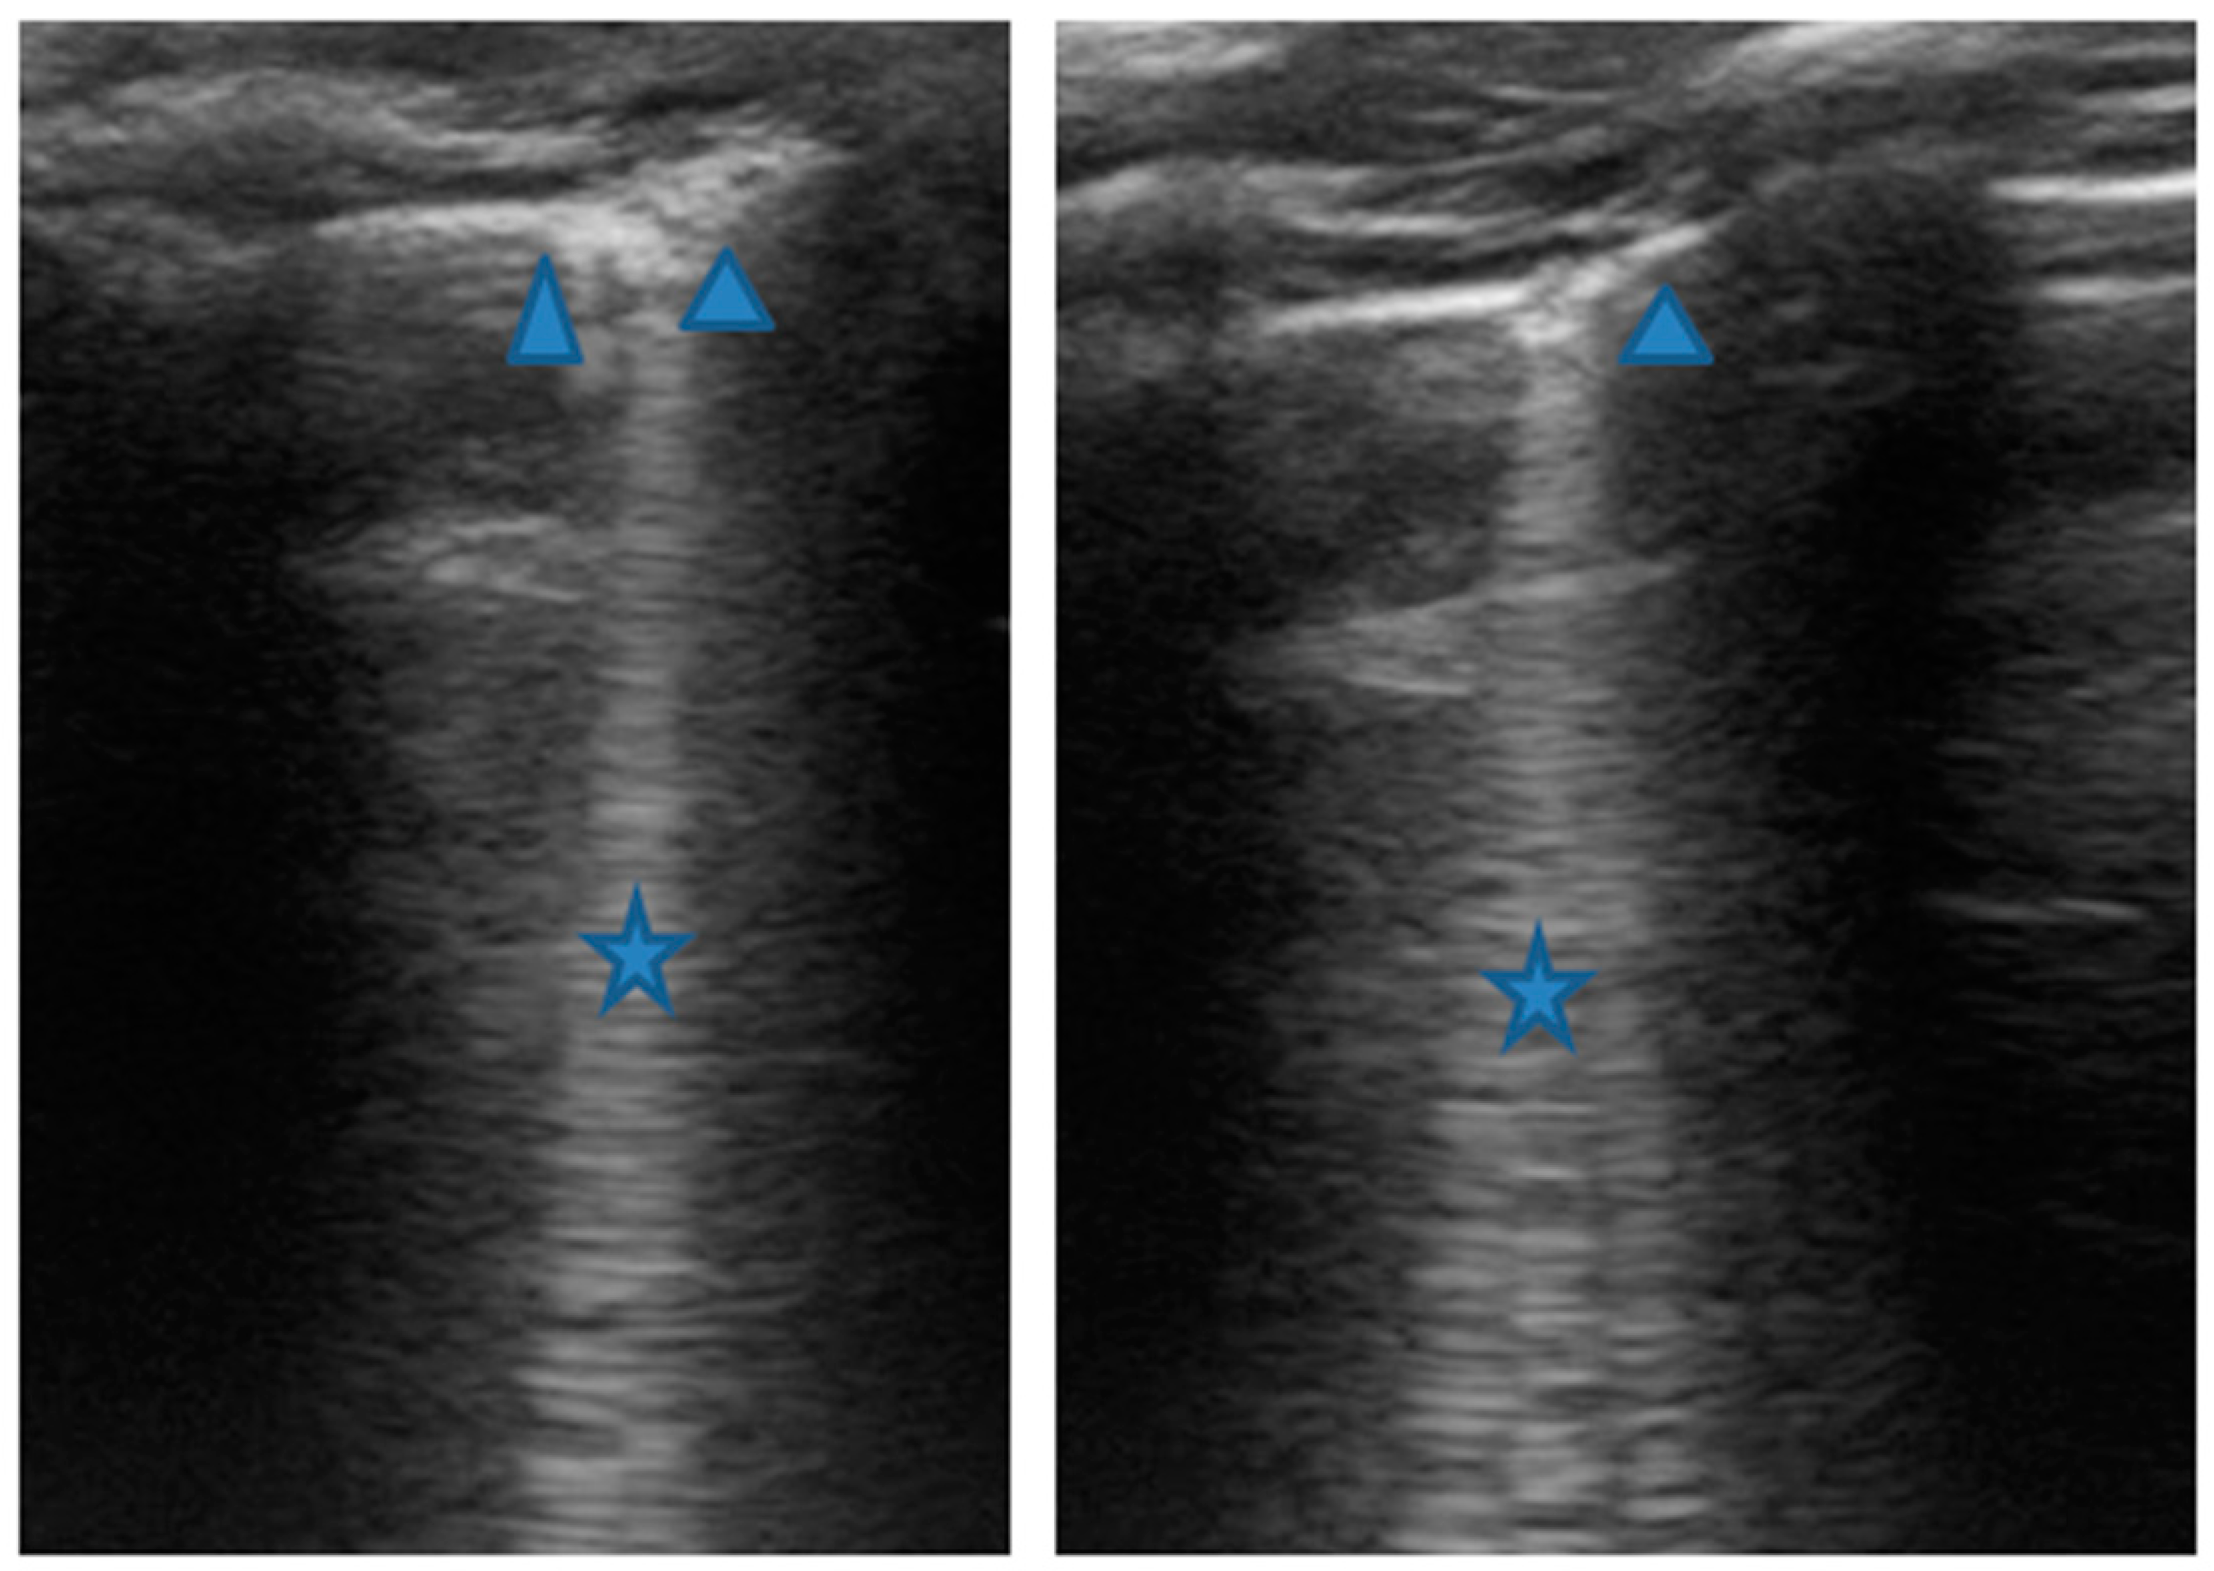

At our hospital, together with the clinical evaluation, we performed a lung ultrasound, which showed the presence of two areas of moderate lung atelectasis, in the right anterior mid-apical and in the left anterior paracardiac site, respectively, associated with sonographic interstitial syndrome (SIS) (Figure 1). LUS excluded the presence of inflammatory/infectious consolidations.

Figure 1.

Grayscale lung ultrasound examination shows: (A): on the right anterior field, mainly in the mid-apical area, consolidation of atelectasis origin (arrow) with static air bronchograms (punctate), and parallel to each other (arrowheads), associated with sonographic interstitial syndrome (SIS), represented by coalescent vertical artefacts or B-lines (asterisks); (B): on the left paracardiac site, consolidation of about 2.5–3 cm of atelectasis nature (arrow) with static air bronchograms (punctate) (arrowheads), associated with sonographic interstitial syndrome (SIS), represented by coalescent vertical artefacts or B-lines (asterisks).

The lung ultrasound follow-up showed complete resolution of the areas of atelectasis after 4 weeks from the start of background therapy, whereas the long vertical artifacts and irregularities of the pleural line persisted.

In our cases (Table 1), particularly in the first three cases—children with asthma not controlled due to an inadequate preventive therapy for age, phenotype, and severity of the clinical picture [1,2]—LUS was highly positive (Figure 1, Figure 3 and Figure 5). It showed the presence of lung atelectasis, which resolved slowly after weeks of therapy of the acute attack and the beginning of adequate preventive therapy. On the contrary, in case 4 and 5—children with asthma well controlled by adequate preventive therapy—LUS was not highly positive (Figure 6 and Figure 7). In fact, it did not show large atelectasis, but a slight SIS in case 4, and a SIS suggestive of viral infection of the small airways in case 5 [14,15].